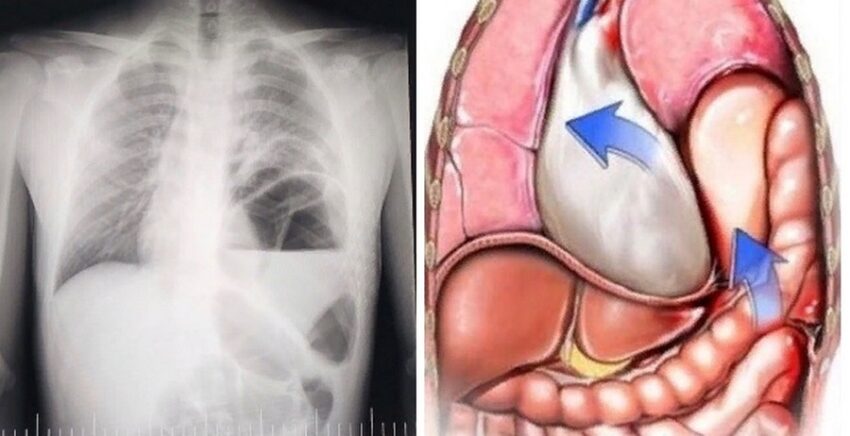

Объясняем, диафрагмальная грыжа – это перемещение органов из брюшной полости (кишечник, желудок и т.д.) в грудную полость через естественное или патологическое отверстие в диафрагме (ложные), а также путем выпячивания истонченного участка диафрагмы (истинные).

Оба ребенка поступили с клиникой острого течения данного заболевания (нарастали симптомы сердечно-лёгочной недостаточности) и были прооперированы в экстренном порядке.

Во время операции врачи установили, что в грудную клетку переместились: желудок, селезенка, поперечная ободочная кишка, сальник и участок тонкого кишечника. Операция прошла успешно, восстановлена анатомическая целостность — устранен дефект диафрагмы. Несколько дней дети находились в отделении реанимации под круглосуточным наблюдением врачей-реаниматологов, которые контролировали такие важные показатели, как артериальное давление, пульс, сатурация, дыхание, а также проводили нутритивную поддержу и обезболивание.